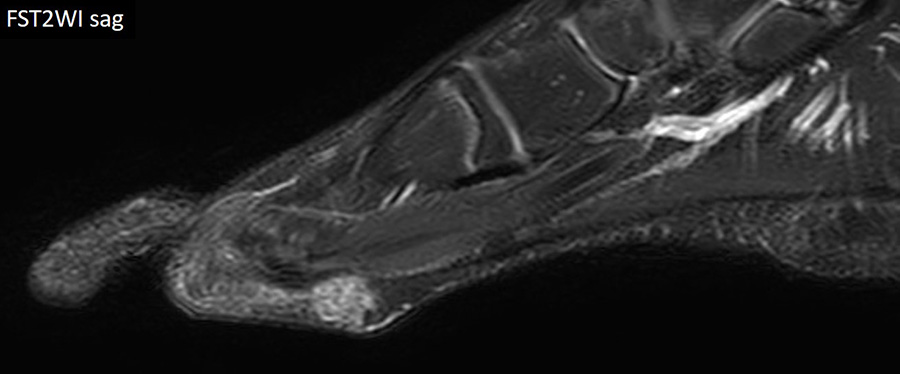

8歳男児 歩行時痛、足底部腫瘤

FST2WI sag

- 【参考症例】